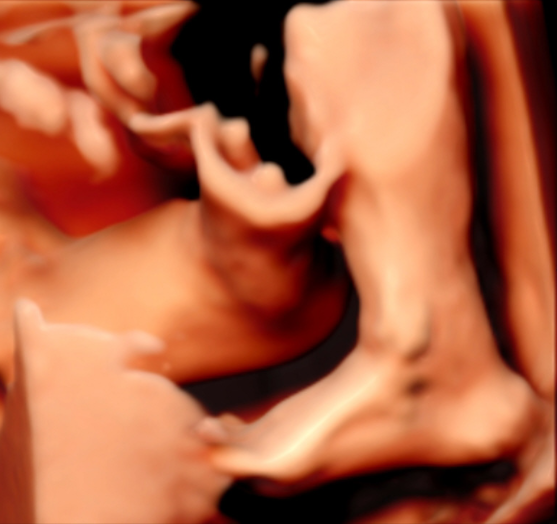

5D智能彩超拥有更高的分辨率和更强的图像处理能力,能够呈现出接近“IMAX电影画质”的细腻影像 。它采用一种被称为“水晶成像”的技术,能够穿透组织,将胎儿的骨骼、器官和组织结构以极其清晰、立体的形态展示出来。这种高清晰度对于观察胎儿微小的解剖结构细节至关重要,例如手指、脚趾、耳廓形态等,有助于医生发现一些在传统超声下不易察觉的细微异常,为排畸诊断提供了更丰富的视觉信息。

4. 温情互动,一次充满感动的“亲子会面”

除了严谨的医学诊断价值,5D彩超也为准爸妈们带来了无与伦比的情感体验。通过高清逼真的动态影像,您可以清晰地看到宝宝的每一个细微表情和动作,仿佛他(她)就在眼前。这份提前到来的“亲密接触”,不仅能极大地缓解孕期的焦虑,更能加深家庭成员与未出世宝宝之间的情感连接,让等待的每一天都充满更具体的幸福感。